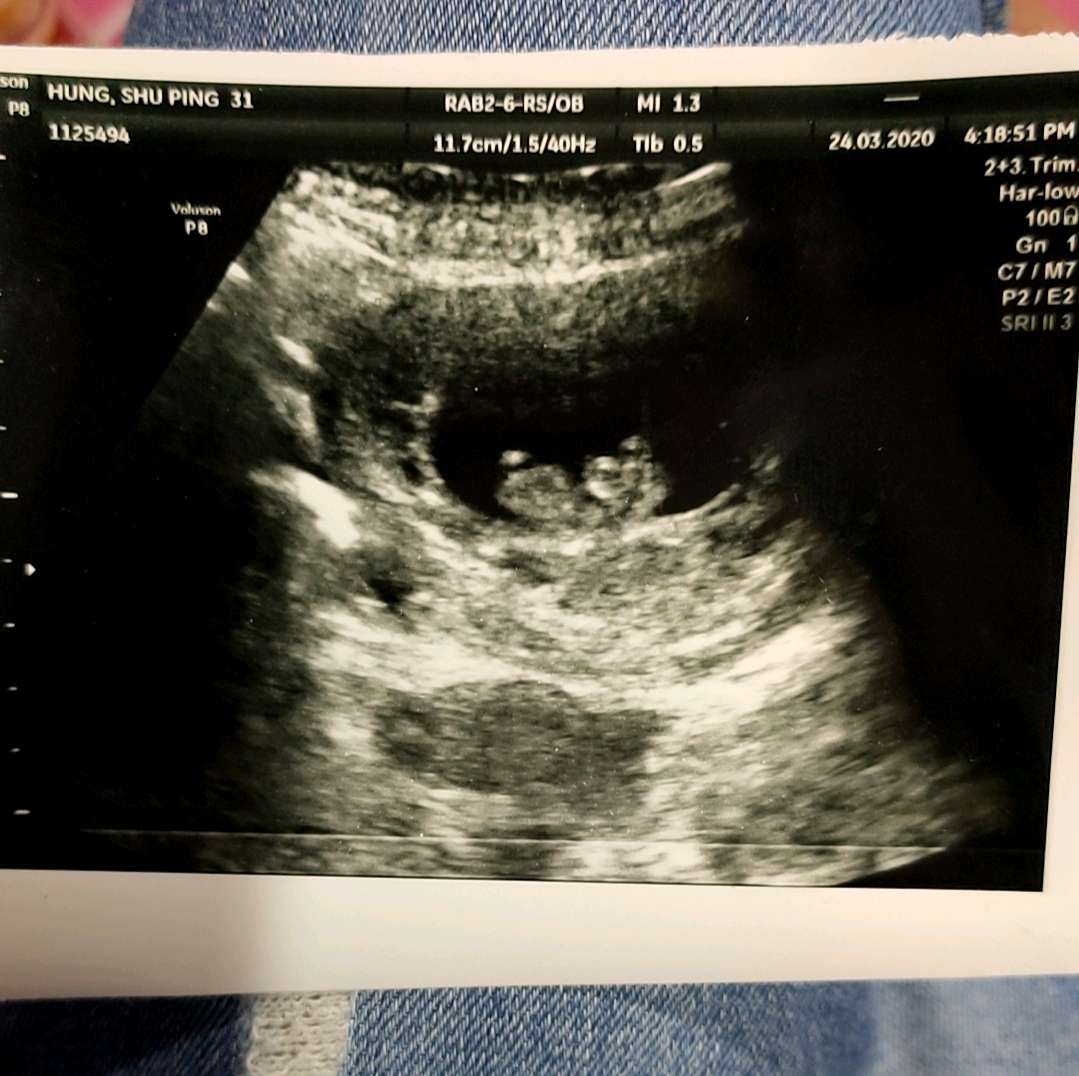

想問各位媽媽們 這是懷孕10週的照片 (2個月10天)但我看不出來寶寶的手腳 有人能看的出來嗎? 新手媽媽很擔心寶寶是否健康 那時也忘了問醫生